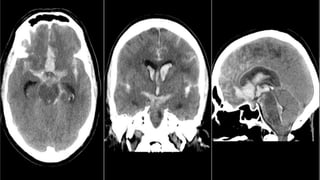

INVESTIGATIONS

• CT scan

INVESTIGATIONS • CT scan •CT angiogram • MRI and MRA • DSA